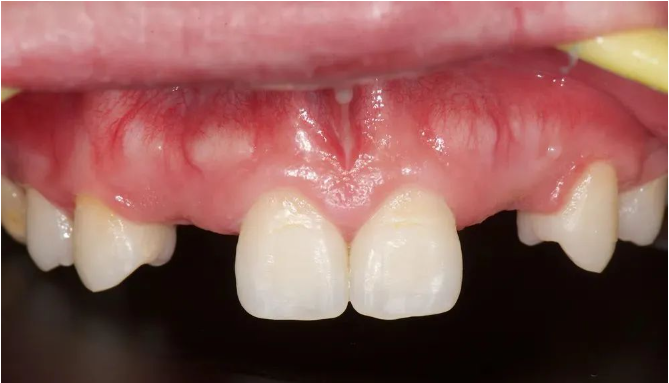

口内检查

12、13、22、23先天缺失

患者缺牙间隙偏宽,唇侧轮廓轻度塌陷,息止颌位切端暴露量正常